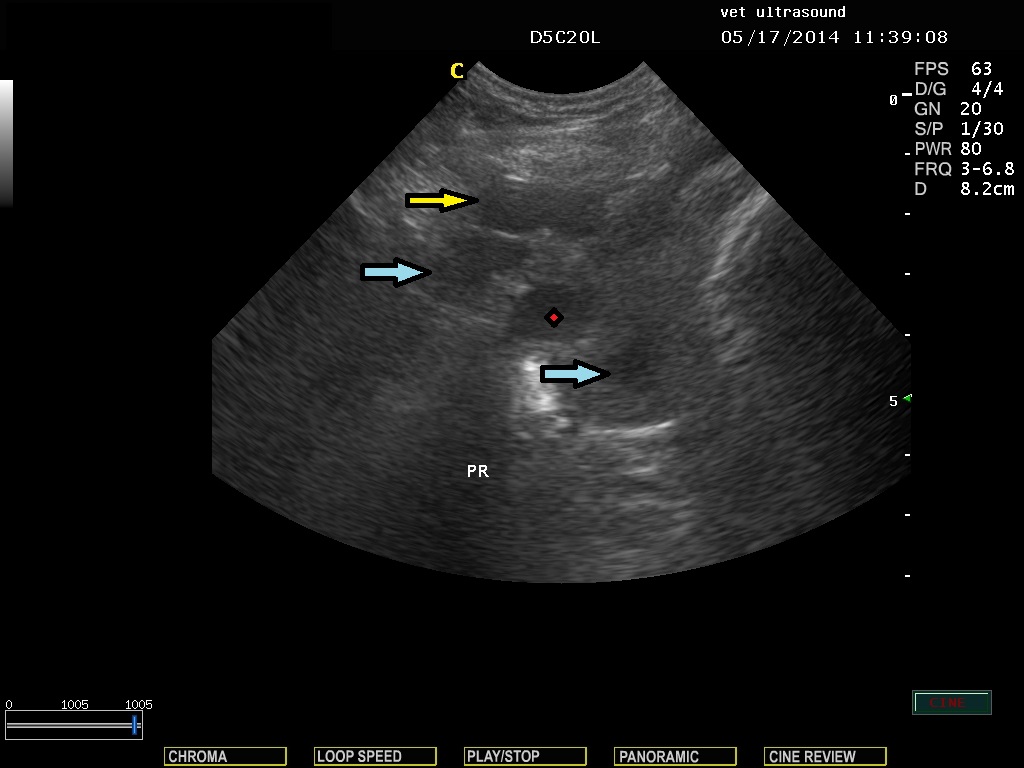

βλέπουμε την διατεταμένη ουροδόχο κύστη και τον προστάτη αδένα. Οι κέρσορες μετρούν το μέγεθος μίας κύστης στο παρέγχυμα του οργάνου.

Το κίτρινο βέλος δείχνει μία παραπροστατική κύστη η οποία καλύπτεται μόνο από την κάψα του αδένα.

Τα μπλέ βέλη δείχνουν δύο ενδοπροστατικές κύστεις

Το κόκκινο αστέρι δείχνει την διατεταμένη ουρήθρα.